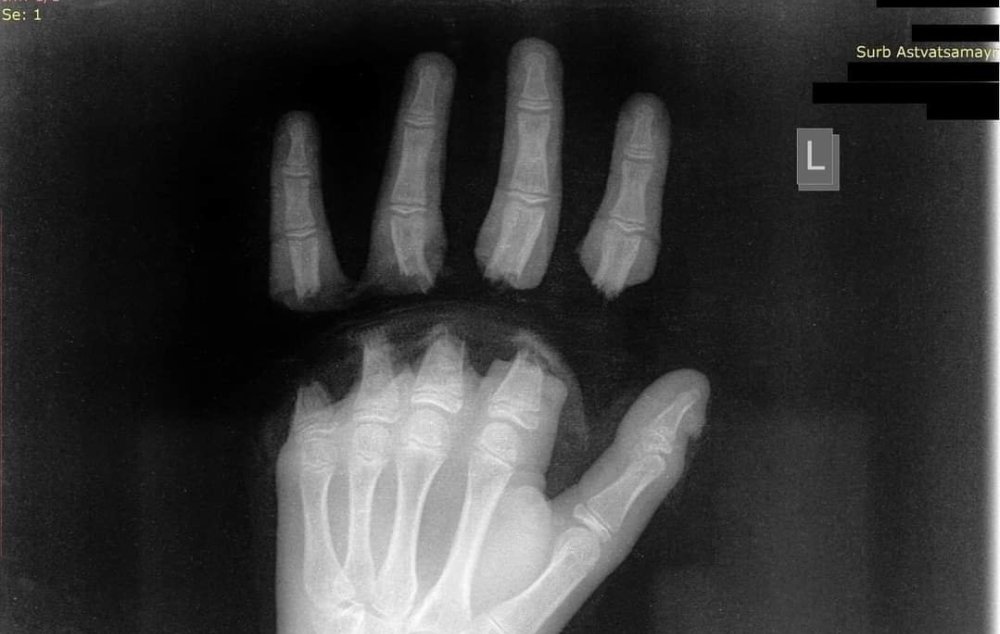

«Սուրբ Աստվածամայր» ԲԿ է ընդունվել 12 տարեկան երեխա՝ ձեռքի չորս մատների ամպուտացմամբ (անդամահատված):

Դեպքը տեղի է ունեցել շան հետ խաղալիս: Կենդանին վզկապի փոխարեն կապված է եղել պողպատե տռոսով, որի մյուս ծայրը փաթաթված է եղել երեխայի մատներին, վազելու ժամանակ այն ձգվել է, ինչի հետևանքով տղայի չորս մատները կտրվել են:

Երեխան տասը ժամ վիրահատվել է, «Սուրբ Աստվածամայր» ԲԿ-ի պլաստիկ վիրաբույժները կատարել են ձեռքի մատների ռեպլանտացիա: